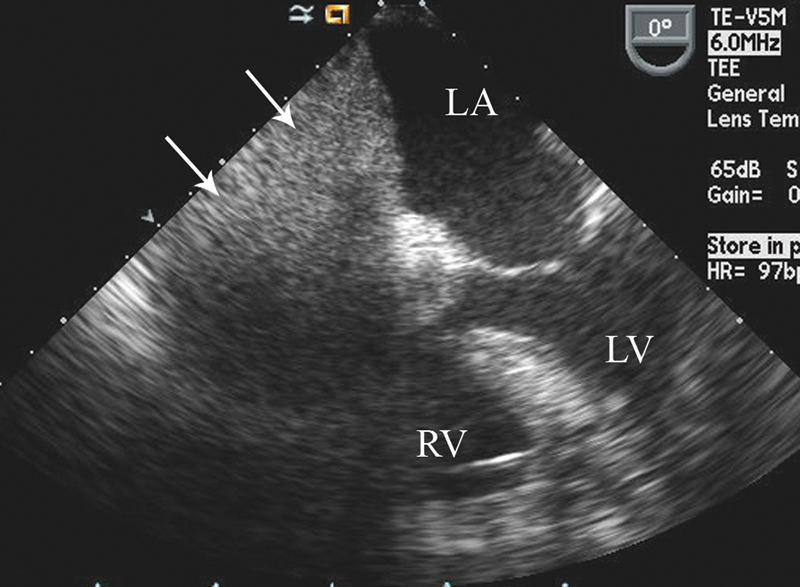

فحوصات تشخيصية لبعض امراض القلب والشرايين التاجية